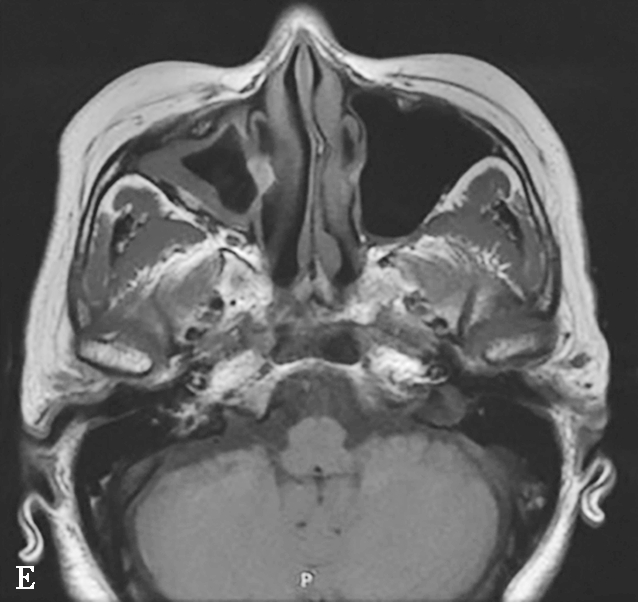

图1-3-20 慢性鼻窦炎

A~C.横断面、冠状面及矢状面CT平扫,示右侧额窦、上颌窦黏膜增厚,窦腔内可见软组织密度影,窦口鼻道复合体狭窄,右侧上颌窦窦壁骨质增生硬化、肥厚;D~F.同一患者横断面MR T 2 WI、T 1 WI及横断面增强T 1 WI,示右侧上颌窦黏膜增厚,呈T 1 WI等信号、T 2 WI高信号影,增强扫描示右侧上颌窦黏膜线样强化